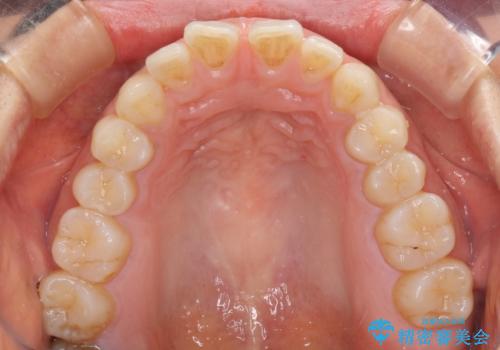

- 上の前歯の隙間を気にして来院された患者様です。

矯正治療により前歯を閉じるという治療を第一選択肢として提案しましたが、期間と費用からオールセラミッククラウンによる補綴治療を行うこととしました。

虫歯もない前歯を削ることは、処置をする者として心苦しいのですが、患者様は矯正治療は選択しないとのことだったので、オールセラミッククラウンにて補綴治療を行いました。